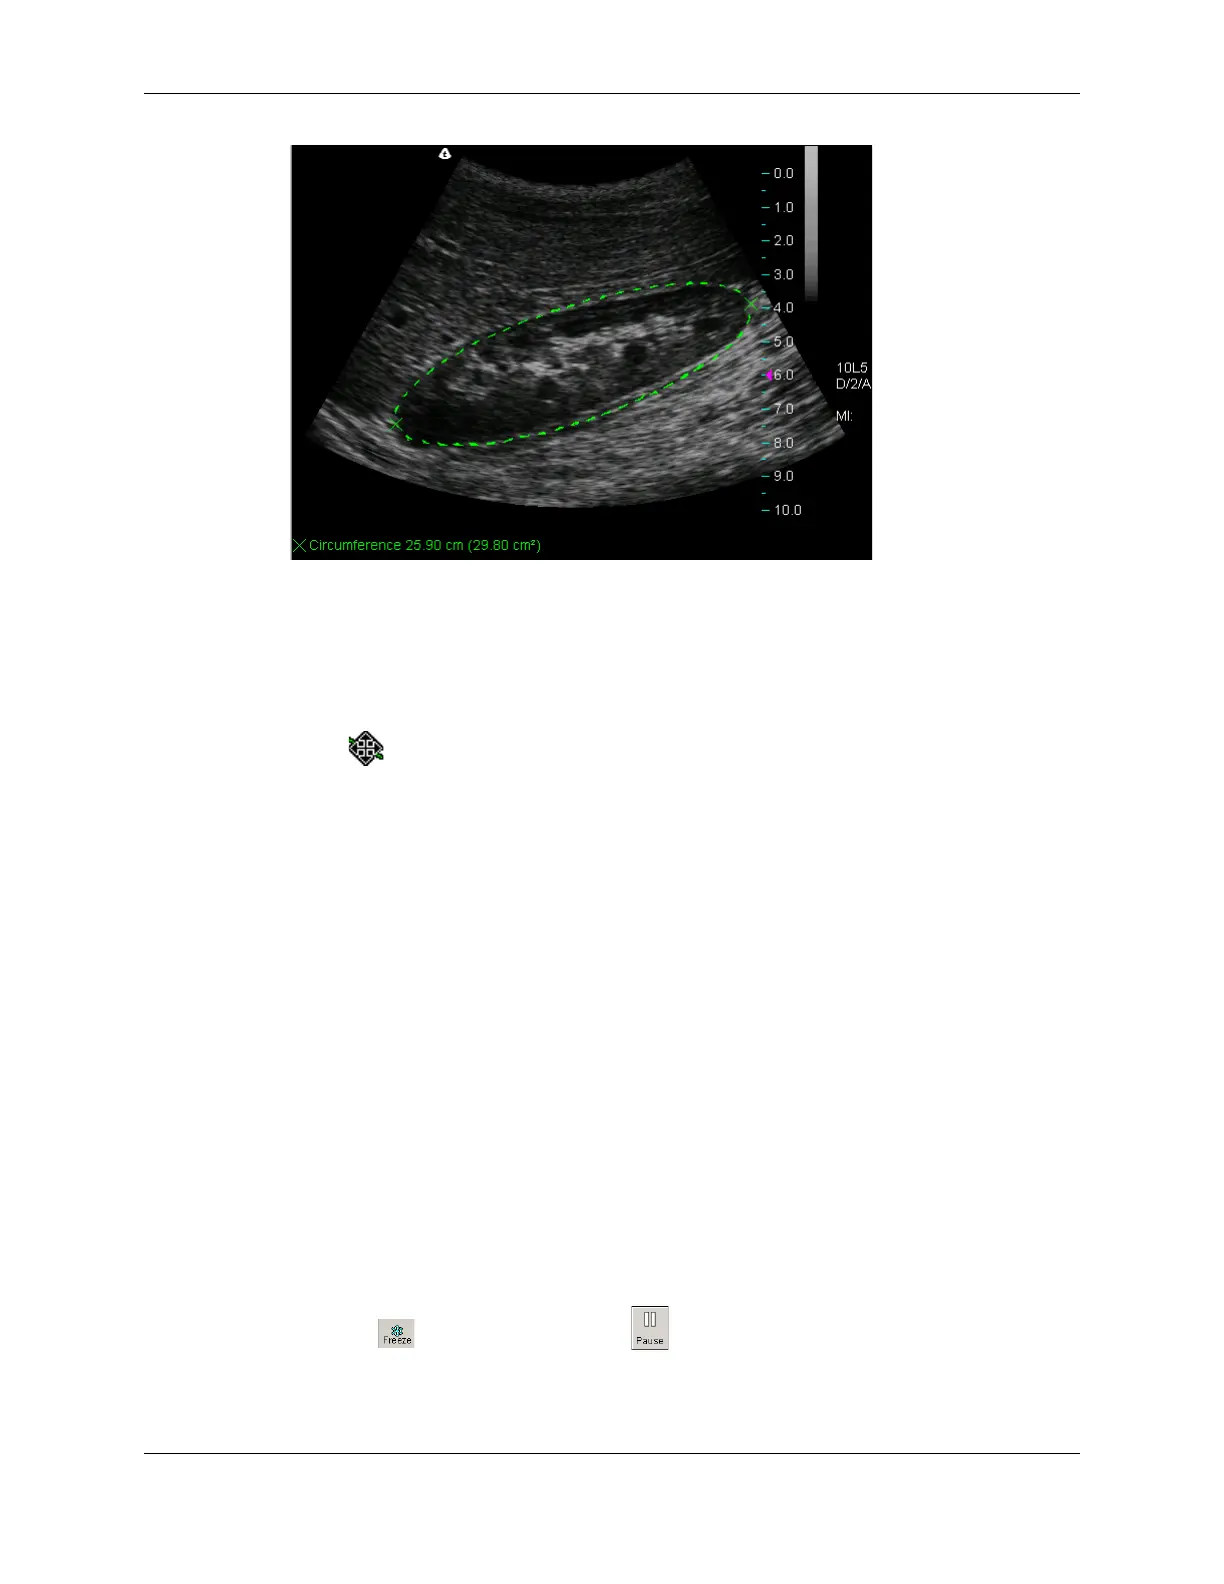

Tracing Areas on the Image

The Terason software lets you trace the contour of any shape on an image to measure the

circumference and area. You can also use the Ellipse tool to measure a circumference or

area (see Measuring Elliptical Circumference and Area on page 154 for instructions.)

You can use the trace tool to:

Trace an irregular shape by sketching the outline

Draw a polygon by clicking on corners of the shape

You can also combine these methods to trace an area on the image.

To trace an area on an image, complete the following steps:

1. Click . If playing a loop, click . The measure tabs for the selected scan mode

are added to the Image Control bar.